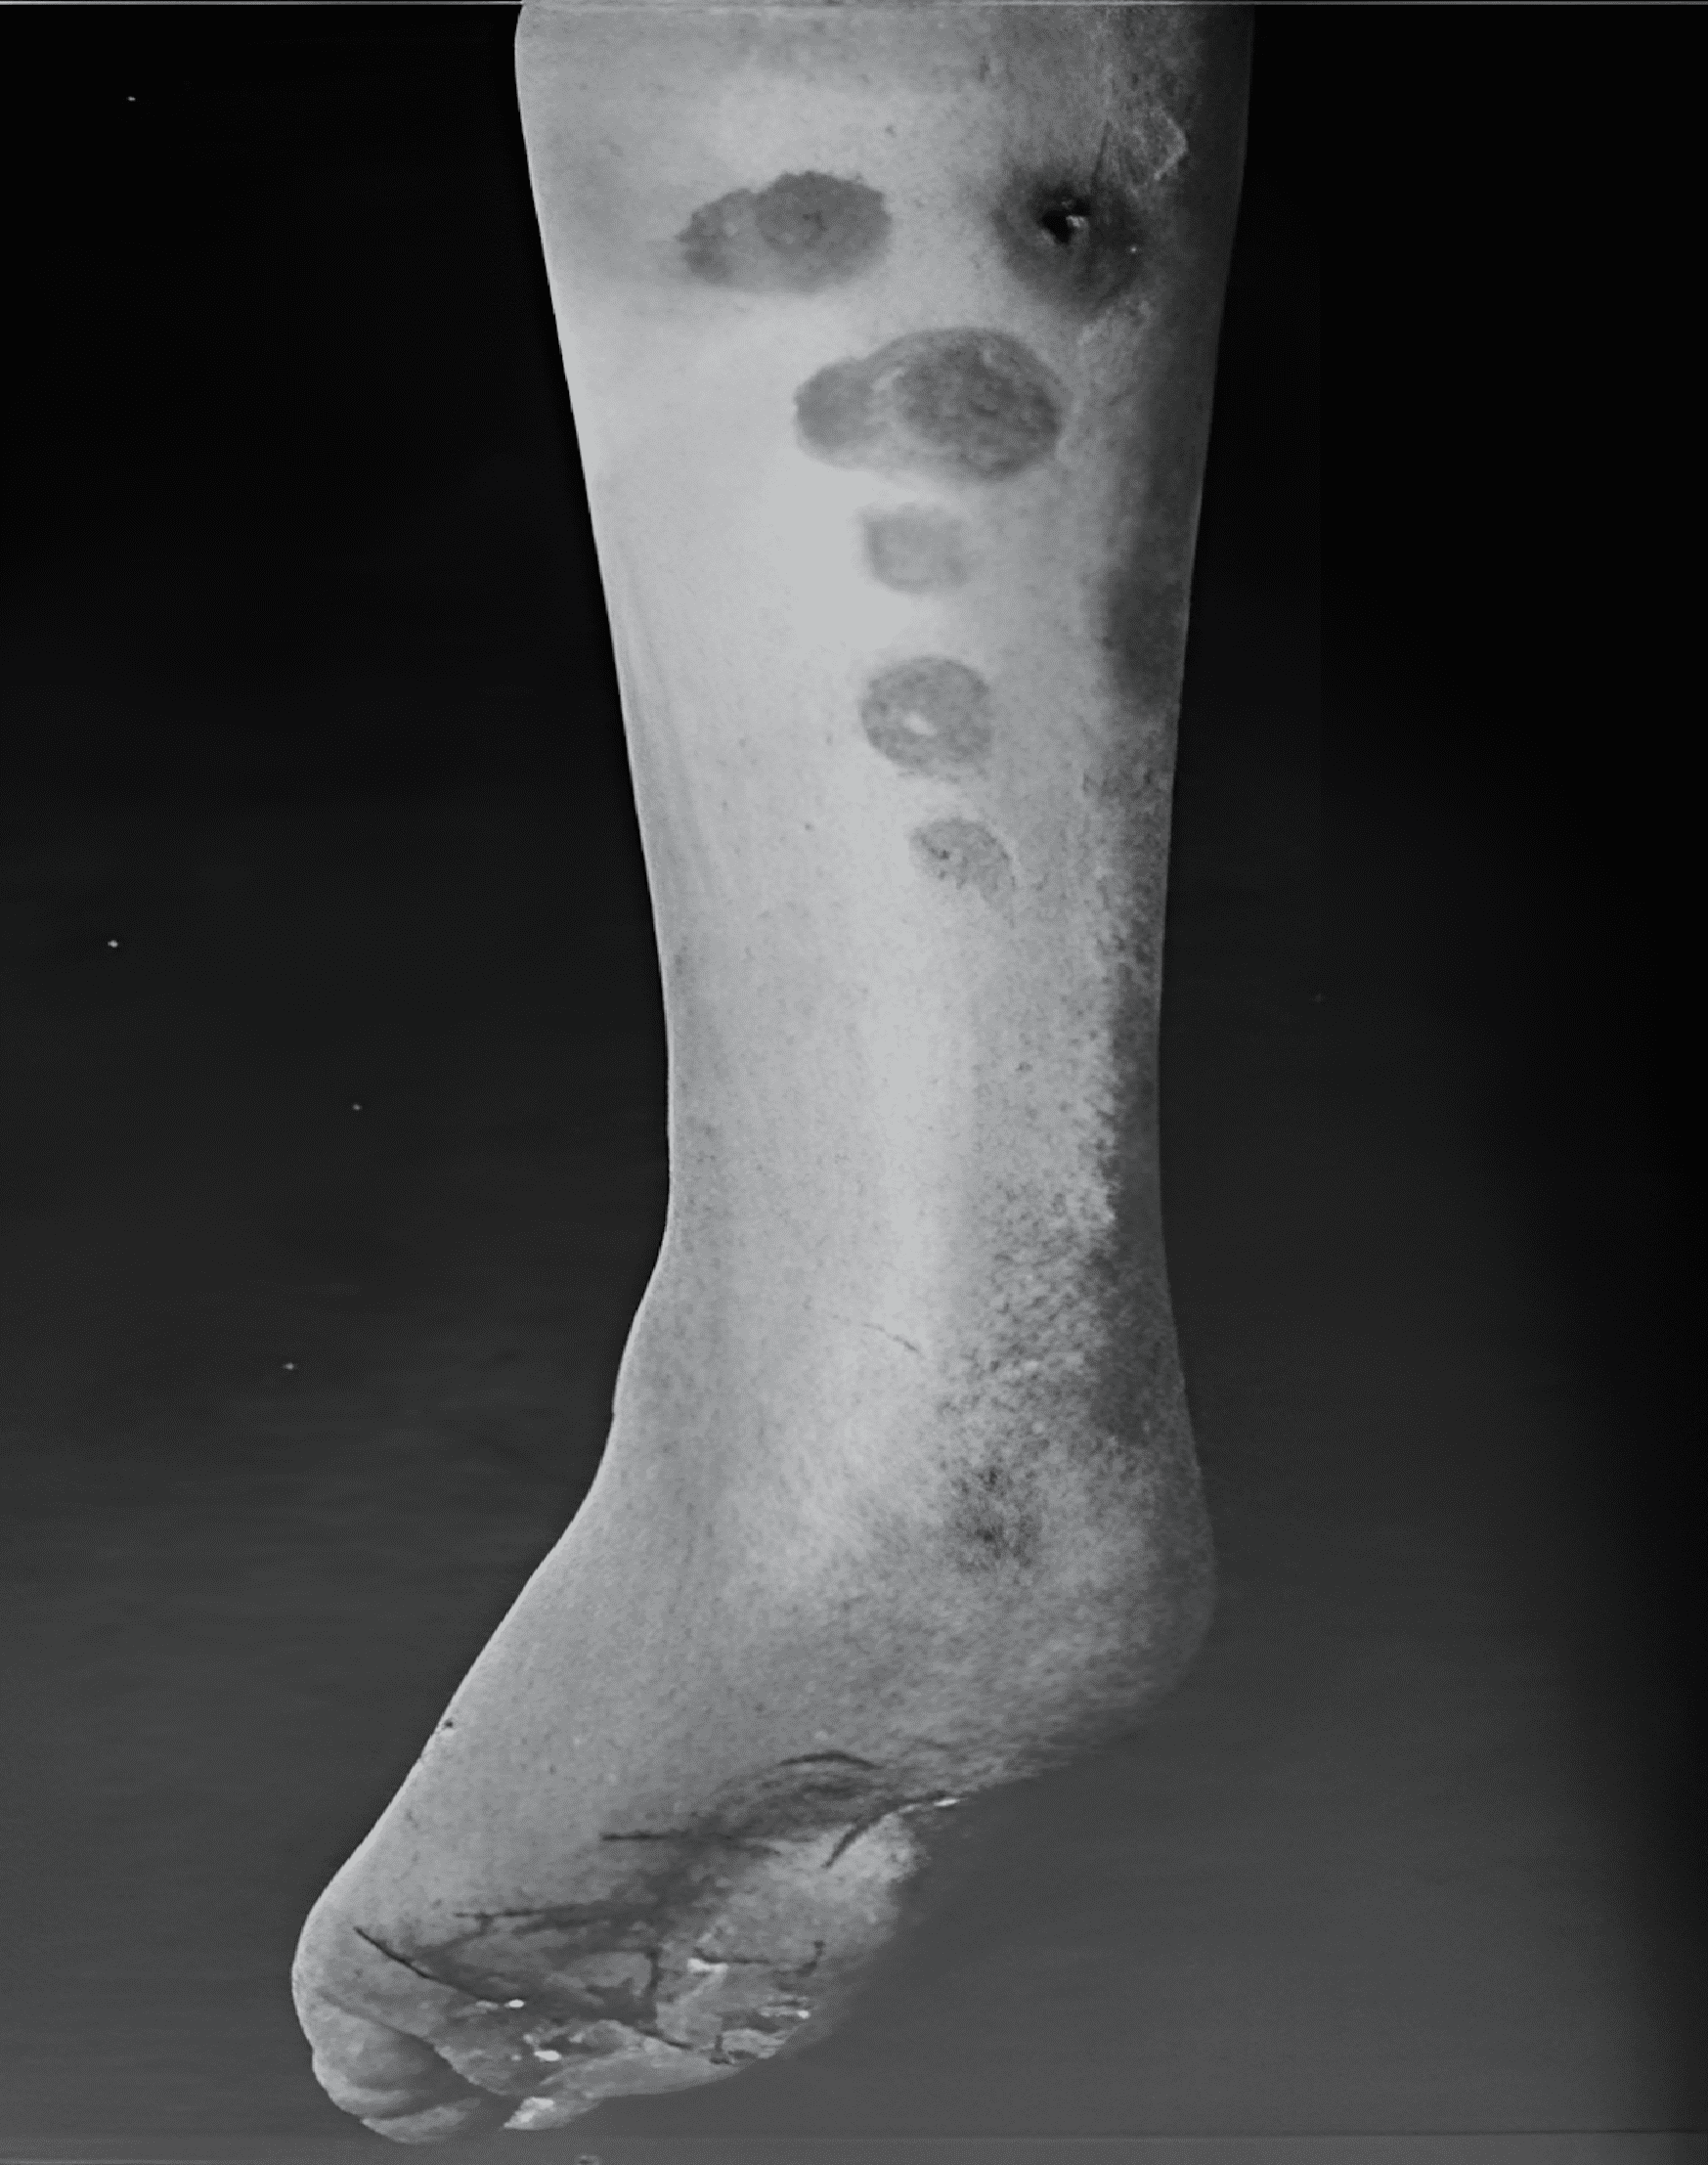

Panniculitis is een aandoening waarbij pijnlijke bultjes of knobbeltjes onder de huid ontstaan, vaak op de benen en voeten. Deze bultjes veroorzaken ontstekingen in de vetlaag onder de huid.

De meest voorkomende plek waar panniculitis voorkomt, zijn de onderbenen (scheenbeen en kuiten) en voeten. Het kan zich ook op andere lichaamsdelen ontwikkelen, zoals de handen en armen, dijen, billen, buik, borsten of het gezicht. Het komt echter veel minder vaak voor in deze gebieden.

Panniculitis kan ook donkere verkleuringen op de huid veroorzaken die lijken op blauwe plekken. Deze vervagen meestal na verloop van tijd zodra de ontsteking afneemt. In sommige gevallen kan het ook verzakkingen op de huid achterlaten. Dit gebeurt als het onderliggende weefsel moet worden vernietigd. Deze verzakkingen kunnen na verloop van tijd verbeteren, maar zijn vaak blijvend.